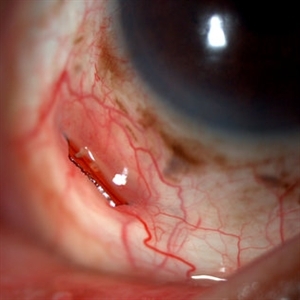

Extrusion of GCV implant

Mar 1 2014 by Homayoun Tabandeh, MD, FASRS

Extrution of gancyclovir implant in a patient with HIV and CMV retinitis 8 years after insertion.

Condition/keywords: extrusion of gancyclovir implant, ganciclovir